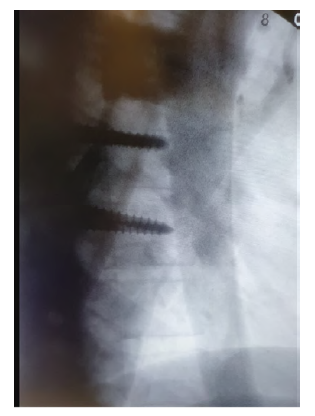

No pós-operatório constatou-se mau posicionamento de material de fixação (Figura 3), pelo que 9 dias depois foi submetido à extração de parafuso protuso em D7 à esquerda sob controlo angiográfico pré e pós-operatório, estando uma endoprótese aórtica torácica na sala para o caso de necessidade de reparação emergente Intra-operatoriamente.

É evidente a presença de material de fixação fazendo protusão sobre a aorta torácica, à esquerda do eixo vertebral.

Não se constatou leak nem alterações da conformação da aorta torácica, não tendo ocorrido qualquer hemorragia pelo trajeto do parafuso (Figuras 4 e 5).

O restante internamento deste doente decorreu sem intercorrências e ficou com indicação para reavaliação imagiológica dentro de 6 meses para exclusão de pseudoaneurisma.